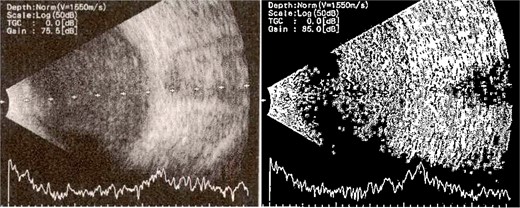

Patient 5: Fifteen days post-phacoemulsification, a 65-year-old Saudi female presented with no light perception (NPL) and severe lid edema (Fig. 9). B-scan revealed vitritis (Fig. 9). Figure 10 showing the B-Scan Ultrasound, illustrates the findings in Patient 5. Computed tomography (CT) scans of the orbit showed pan ophthalmitis (Fig. 11). She received intravitreal antibiotics immediately, followed by a pars plana vitrectomy.

B-scan ultrasound showing sever vitreous echoes and vitreous abscess in patient 5.